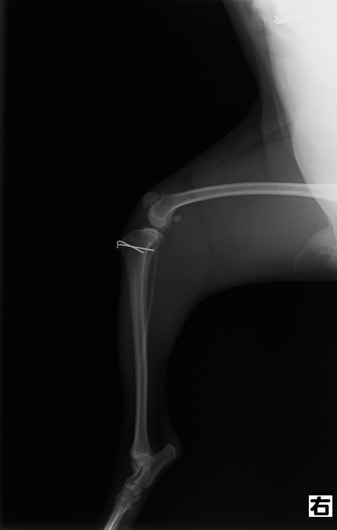

■ 症例24 キャバリア 7か月

左右膝蓋骨内方脱臼(左:グレードⅣ 右:グレードⅢ)

以前から左右後肢の跛行が認められ、整形外科学的検査・レントゲン検査により左右の膝蓋骨脱臼が認められた。症状が重度である左膝の膝蓋骨脱臼整復術を行った。外科手技は縫工筋及び内側広筋の解放、脛骨粗面の外側転位、滑車ブロック形造溝術、内外側関節方の縫縮を実施した。術後一か月時点で、左の膝蓋骨は安定しており経過は良好である。

本症例は成長期における重度の膝蓋骨脱臼であり、術後の再発の可能性もあるため、経過をしっかりと観察していく必要がある。また、今回手術を実施していない右膝に関しても経過を観察し、手術を検討していくこととする。